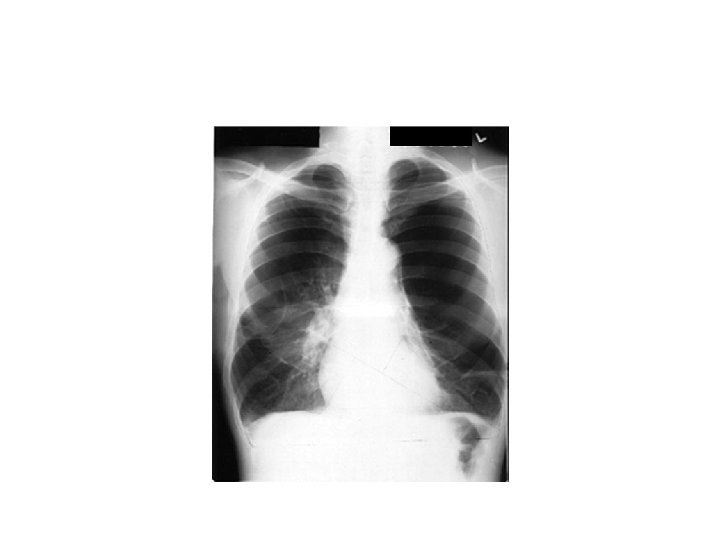

CXR

COR Pulmonale

Emphysema